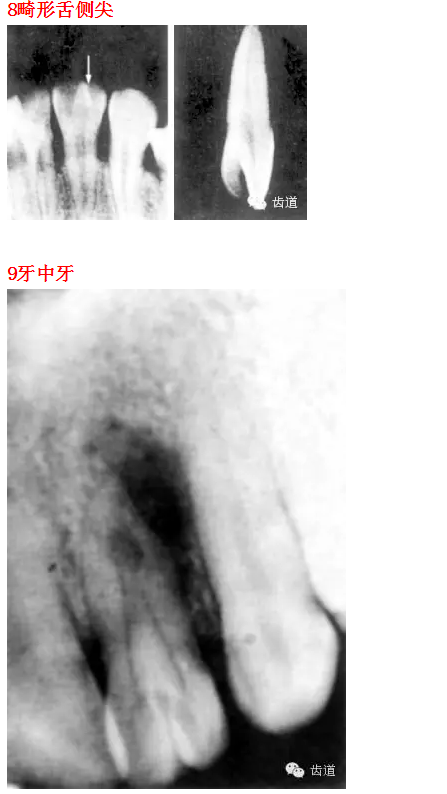

26種口腔病變X光片